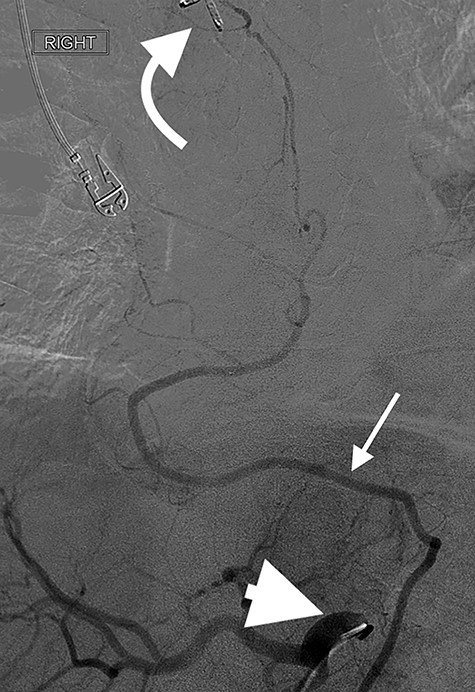

Angiography showing extravasation at the anastomosis. Curved arrow = OG anastomosis; Red arrow = contrast extravasation; Arrow MC = microcatheter.

Eight days later, he represented with an upper gastrointestinal bleed with massive haematemesis requiring immediate intubation for airway protection. Computer tomography angiography was unremarkable and an emergency gastroscopy revealed an extensive amount of blood and clot in the oesophagus and gastric conduit (limiting the view), but no active bleeding point. Conservative treatment in the Intensive Care Unit (ICU) with blood transfusion, proton pump inhibitors and life support were implemented. Another large bleed occurred 2 days later and a repeat gastroscopy revealed a non-bleeding visible vessel at the OG anastomosis and a haemostatic clip was applied. However, over the next 10 days, the patient remained blood transfusion dependent and had two further endoscopies. The first was unremarkable, but the second endoscopy re-demonstrated the luminal vessel at the OG anastomosis, with no evidence of the previously placed clip. This was felt to be the cause of his intermittent and problematic bleeding, so another haemostatic clip was attempted, resulting in pulsatile, moderate volume arterial bleeding. The procedure was abandoned and the patient transported immediately to the Interventional Radiology Suite. Right femoral access was obtained and angiography performed. The thoracic aorta was normal, so the celiac trunk was cannulated and angiography of the right gastro-epiploic artery performed (Fig. 1), revealing active extravasation of contrast at the OG anastomosis as shown in Fig. 2. A microcatheter was advanced along the length of the right gastro-epiploic artery to the OG anastomosis and coil embolization was performed (Fig. 3). Care had to be taken to ensure that the embolization was as distal as possible to limit the risk of ischaemic complications. The patient required lengthy ongoing care in the ICU for organ dysfunction but remained hemodynamically stable after embolization without evidence of conduit ischaemia. His hospital stay was obviously lengthy, but he was ultimately transferred to a rehabilitation unit.

Oesophagectomy is a major operation with significant perioperative morbidity. Respiratory and cardiac complications, along with gastric conduit ischemia and anastomotic leak, tend to dominate [3]. However, bleeding complications apart from those occurring intra-operatively are rarely reported [1, 2]. We present a unique case of an anastomotic bleed from a terminal branch of the gastro-epiploic vascular arcade. While the origin of this vascular arcade is a defined vessel (right gastric-epiploic artery) visible to the naked eye, the terminal portion is comprised of submucosal arterioles and capillaries and often devoid of a visible vessel [4]. However, as shown in Fig. 1, vascular supply to the terminal portion of the gastric conduit is present and can be abundant. The bleeding in this case likely occurred from incorporation in the anastomosis of either an invisible submucosal arteriole or the terminal portion of the right gastro-epiploic artery hidden within omental tissue. It is our standard practise to construct the OG anastomosis with the EEA circular stapler. It is common surgical knowledge that the oesophageal wall is thick [5] and has been our practise to use the 4.8-mm EEA staple height. There are several descriptions in the literature about this anastomotic technique and most recommend this staple height [6–8]. However, we believe that the higher staple height may have contributed to the bleeding issue in this case as there may have been insufficient compression of a submucosal arteriole. While it is impossible to be certain if a lower staple height would have prevented this situation, this case has resulted in our change to use the 3.5-mm EEA. In addition to this, we have become more meticulous in ensuring that the portion of the great curvature to be used for the anastomosis is cleared of excessive omental tissue to be sure no visible vessel is present that may get caught in the anastomosis.